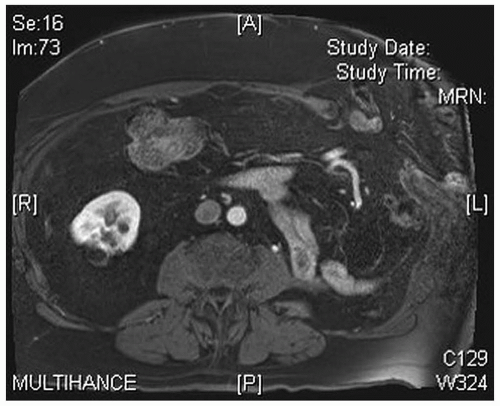

We routinely obtain a CT scan of the abdomen using oral and IV contrast to assess the layers of the abdominal wall, to measure the size of the defect, and to screen for any other intra-abdominal pathology (such as a recurrent cancer) as dictated by the patient’s history. Any midline hernias would be documented (though typically not addressed) at the time of the flank repair (FIG 2).